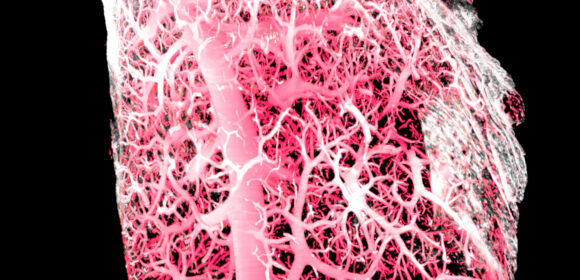

Art of Science is an annual competition and exhibition of still and moving images captured by WEHI scientists during their research into cancer, infection and immunity and healthy development and ageing.